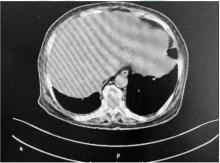

气球状细胞黑色素瘤(BCM)是原发性皮肤黑色素瘤中罕见的组织学类型,文献报道极少,现报道BCM肝转移患者1例,通过介绍该患者的临床病理资料,并观察其组织学形态及免疫表型特征,提升临床医师和病理科医师对此类皮肤转移癌的早期诊断及治疗水平,减少误诊和漏诊。